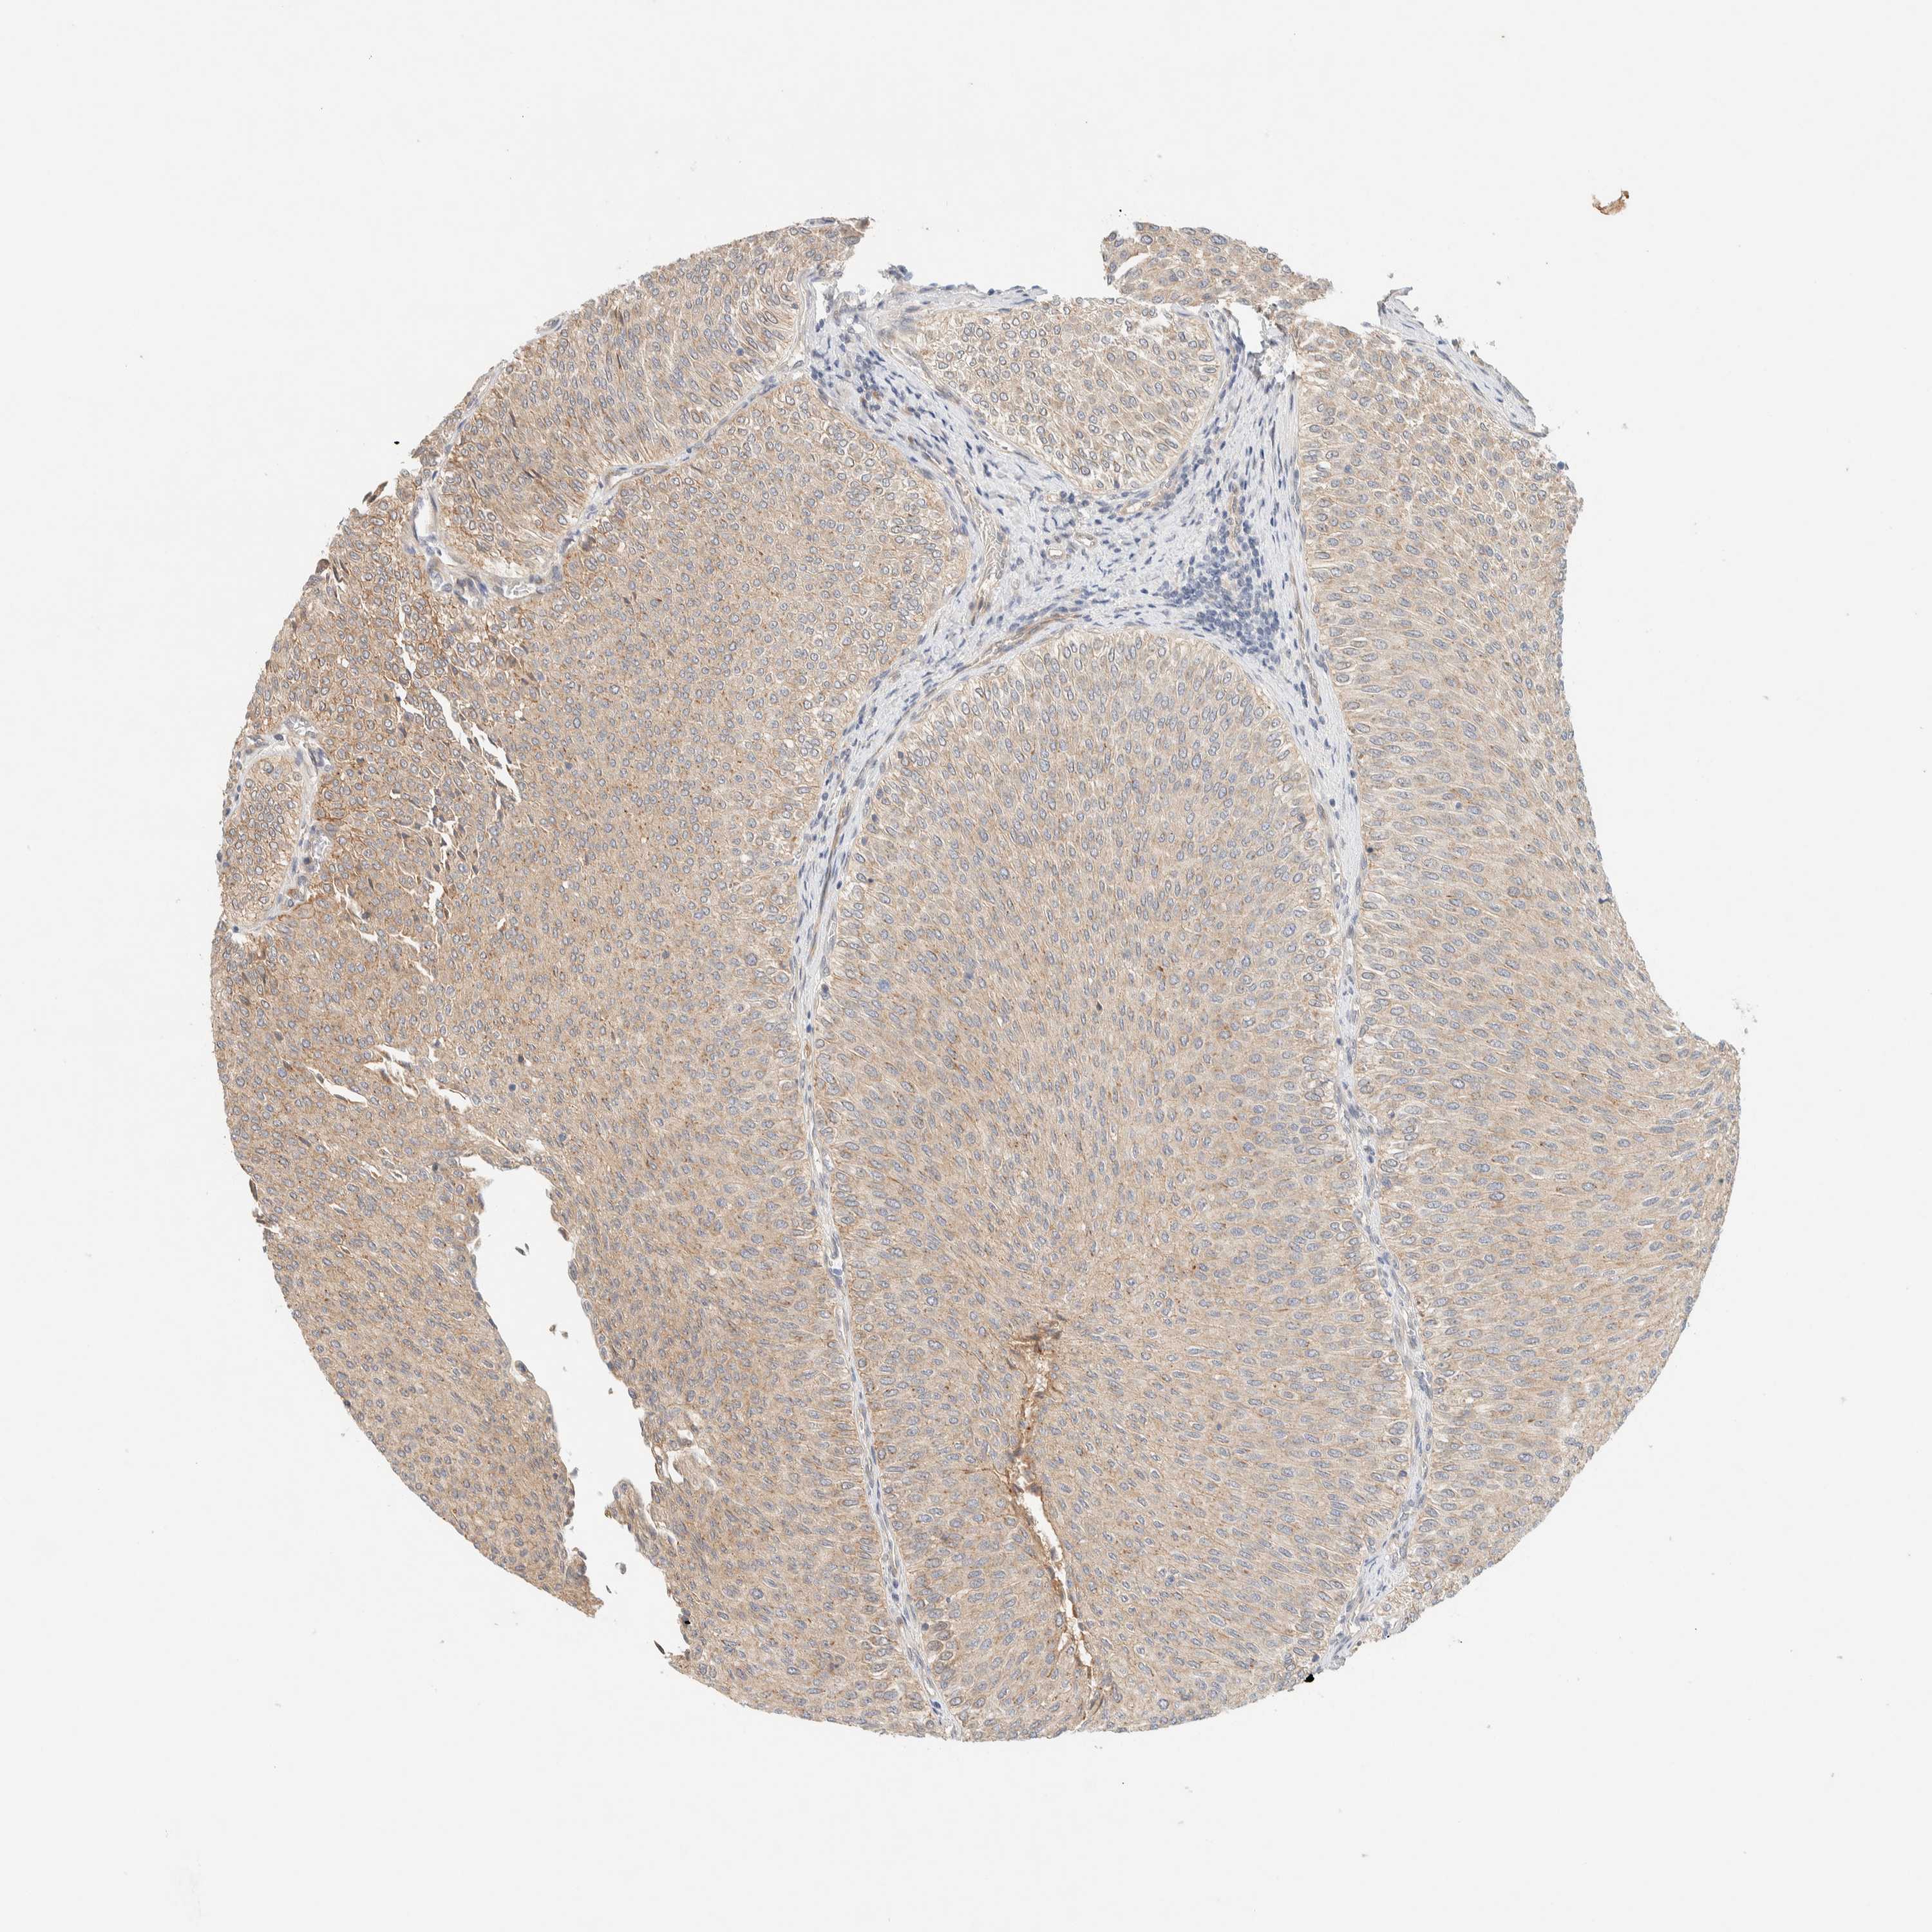

UROTHELIAL CANCER - Protein expressioni

A mouse-over function shows sample information and annotation data. Click on an image to view it in a full screen mode. Samples can be filtered based on level of antibody staining by selecting one or several of the following categories: high, medium, low and not detected. The assay and annotation is described here.

Note that samples used for immunohistochemistry by the Human Protein Atlas do not correspond to samples in the TCGA dataset.

Antibody stainingi

Antibody staining in the annotated cell types in the current human tissue is reported as not detected, low, medium, or high, based on conventional immunohistochemistry profiling in selected tissues. This score is based on the combination of the staining intensity and fraction of stained cells.

Each image is clickable and will lead to virtual microscopy that enables deeper exploration of all samples and also displays staining intensity scores, fraction scores and subcellular localization as well as patient and tissue information for each sample.

Antibody HPA001869

Antibody HPA023882

Staining

High

Medium

Low

Not detected

Intensity

Strong

Moderate

Weak

Negative

Quantity

>75%

75%-25%

<25%

None

Location

Nuclear

Cytoplasmic/membranous

Cytoplasmic/membranous,nuclear

Urothelial carcinoma, High grade

Urothelial carcinoma, Low grade